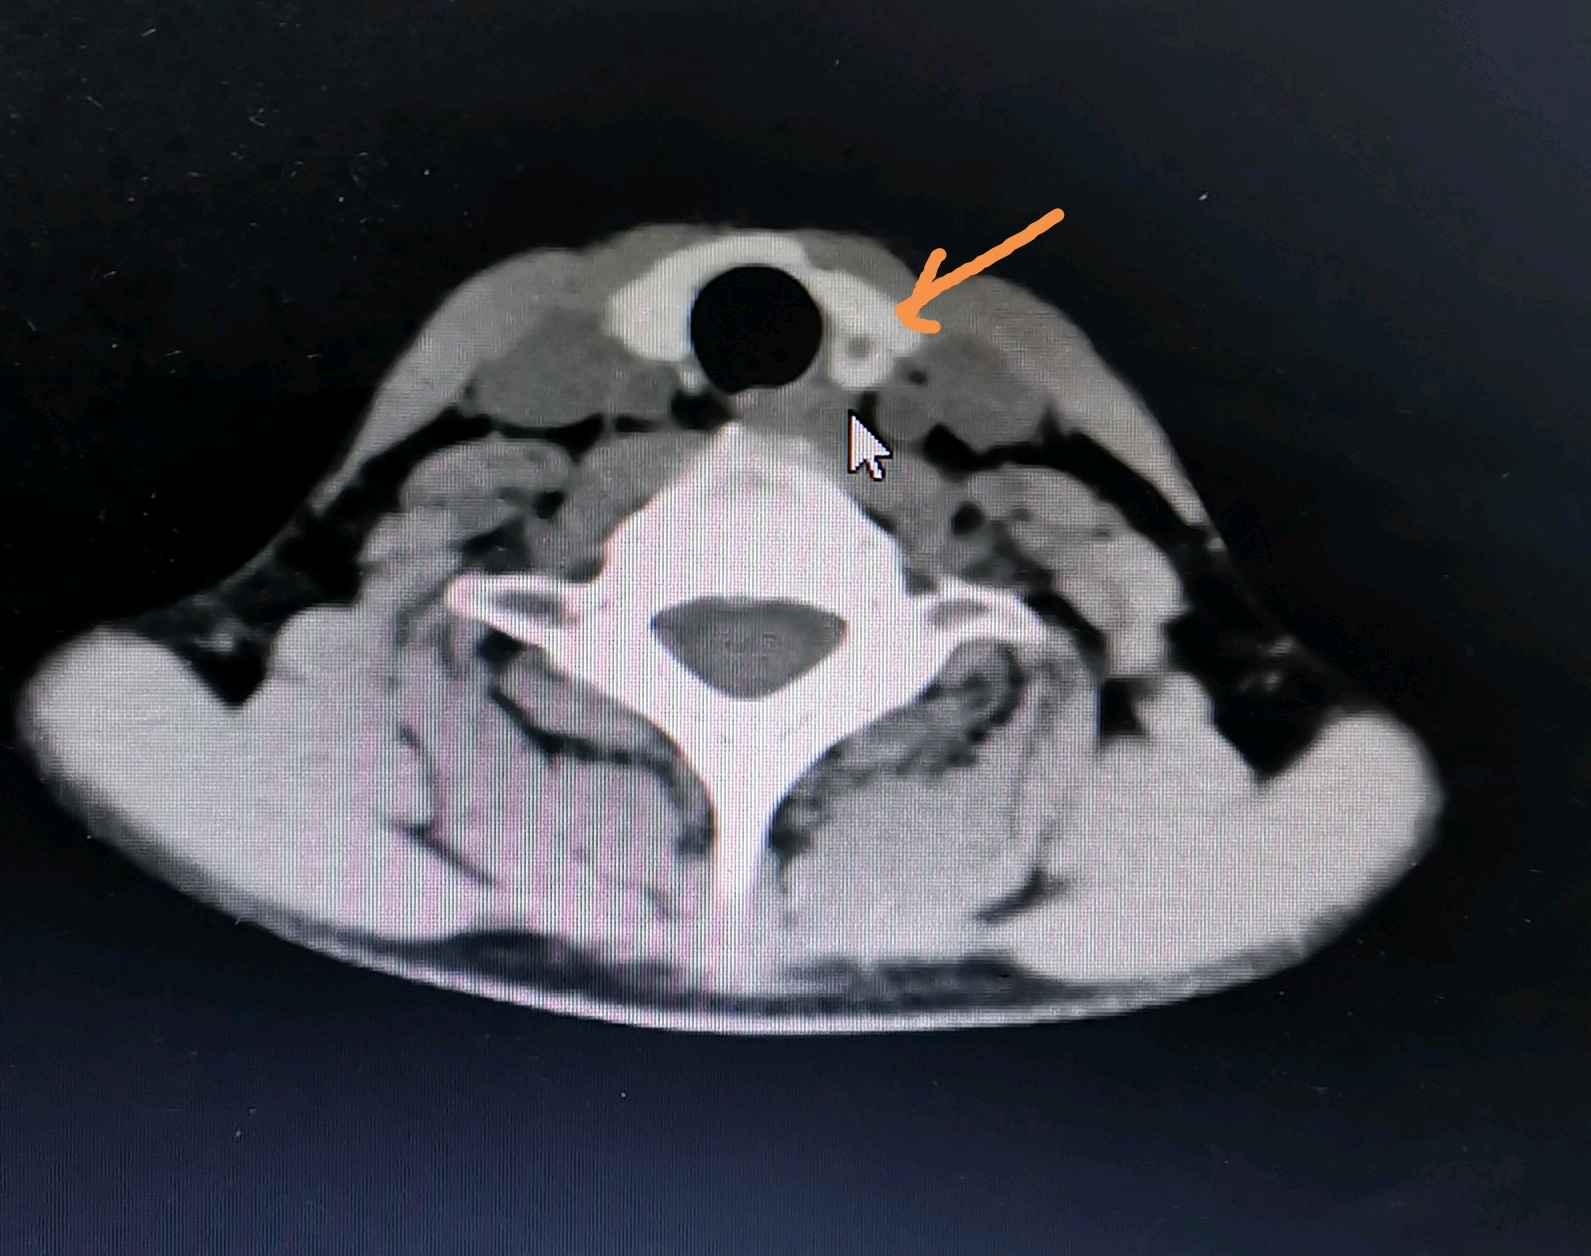

上周,一个同事的中学同学由于体检发现甲状腺结节,省内两家三甲医院的B超提示IVb级,患者非常着急,咨询疫情情况下,能否安排手术。我们经过排除新冠肺炎的相关检查后,安排了手术,术中切下左侧甲状腺腺叶及峡部,解剖保留好左侧喉返神经及上下两个甲状旁腺,术中快速冰冻切片回报为甲状腺微小乳头状癌(3mm),未侵及包膜(上图中鼠标所示白色结节处,下图CT中箭头所示处)。为安全起见,探查清扫了同侧的气管食管沟内(IV区)淋巴结,回报为阴性。术后第二天即拔除了引流管,又观察了一天就出院了。患者感觉恢复满意,声音质量也完好,而且正好在学校还没正式开学的时候就做了,避开了接送照顾孩子上学的繁忙阶段。何况,这种疫情非常时期,住院还是一人一间,相当享受了单间待遇,在平时是不可想象的。